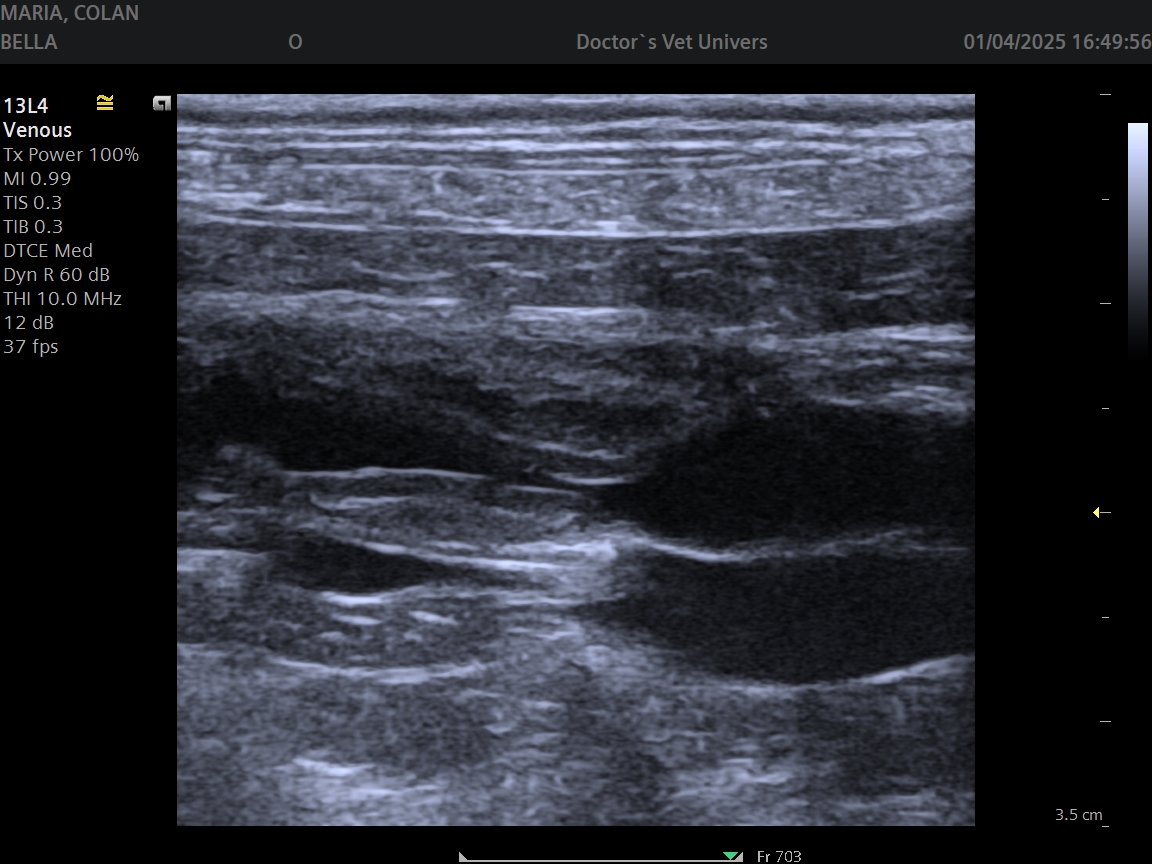

Angioplastia şi Stentarea în Boala Ocluzivă Ateromatoasă a Aortei Infrarenale (patologie extrem de rar întâlnită) la un câine de 16 ani realizată cu succes în premieră în România (şi rar efectuată la nivel internaţional) de către echipa AvantGarde CardioTeam în cadrul Laboratorului de Radiologie Intervenţională Veterinară “Doctor’s Vet Univers” Bucureşti, România.

Angioplasty and Stenting in Atheromatous Occlusive Disease of the Infrarenal Aorta (extremly rare diagnosed pathology) in a 16 years old dog successfully performed for the first time in Romania (and rarely effectuated internationally) by the AvantGarde CardioTeam in the Veterinry Interventional Radiology Laboratory “Doctor’s Vet Univers” Bucharest, Romania.